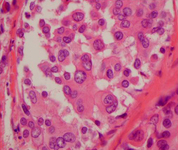

Histopatología del carcinoma lobular in situ (CLIS) pleomórfico

Cortesía del Dr. Sunati Sahoo, University of Louisville; utilizada con autorización

Ver esta imagen en el contexto de la/s siguiente/s sección/es: